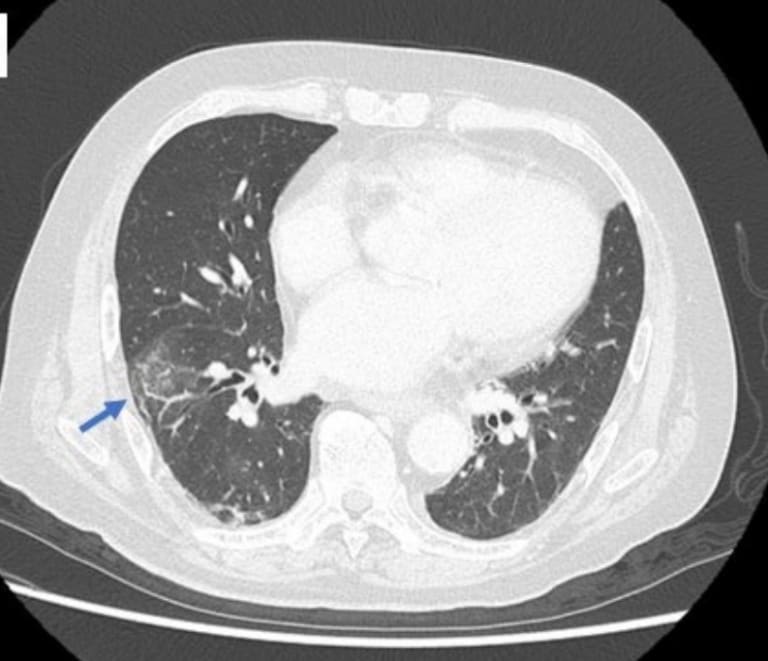

Abb. 1a: Die Computertomographie zeigt körnige und interstitielle Schatten in der Lunge.

© Navano T et al. CMAJ 2025; 197(31): 1004-1005